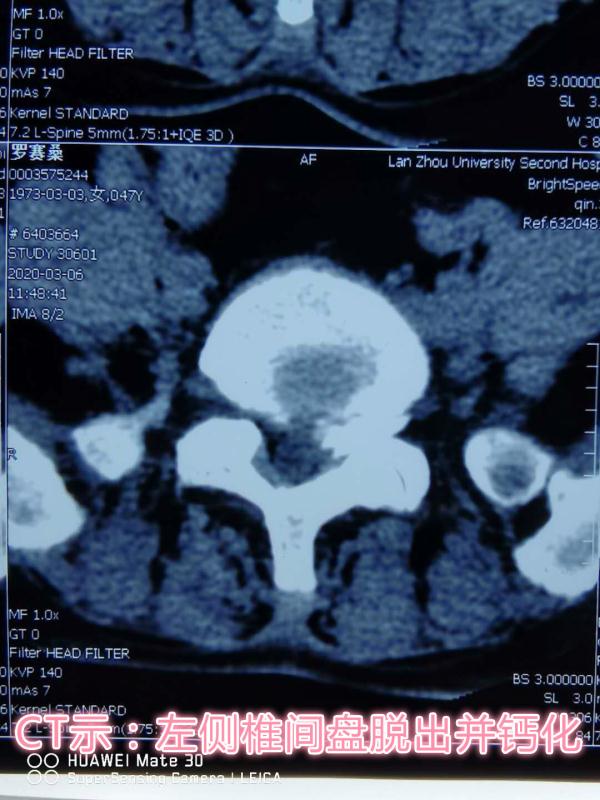

患者,女性,47岁,左下肢疼痛伴麻木1年,加重两月。入院后,骨科医护团队立即完善相关检查,仔细察看患者病情发展情况,为其制定了精准的治疗方案,同时向患者及家属详细讲解了手术的优势及术后的注意事项,患者及家属表示理解并同意手术。术中一切顺利,术后患者次日即可下地活动,大大缩短了传统Tlif术后需卧床三月的修复时间。